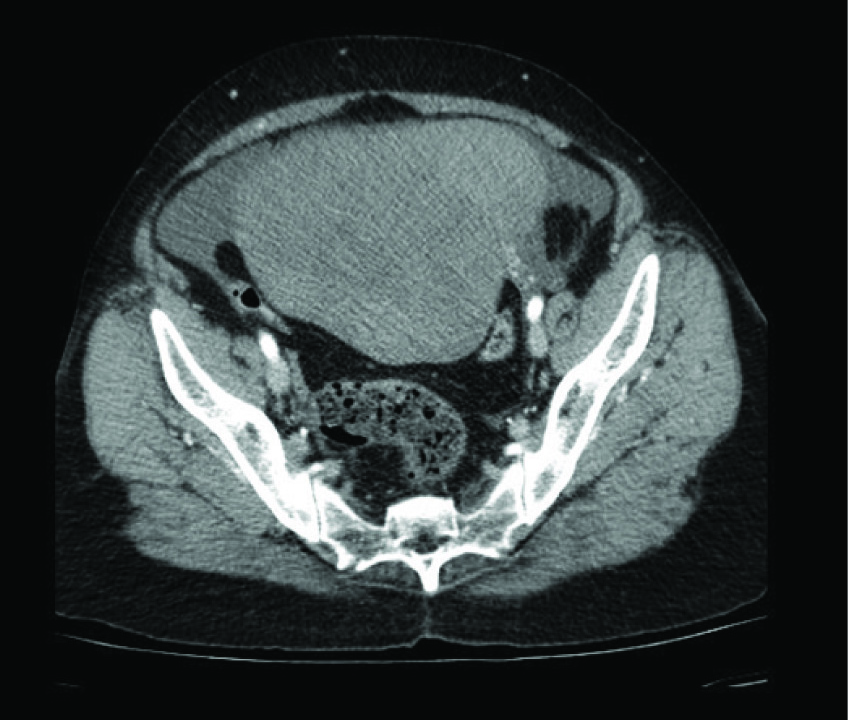

A 53-year-old lady, (P2, L2) who had attained menopause 10 y back, presented with history of abdominal distension for 1month which was associated with dull aching lower abdominal pain. She had no other systemic or menstrual complaints. She was moderately built and nourished and there was no evidence of any generalized lymphadenopathy on general examination. Blood pressure recorded was 150/100mm Hg. On per abdominal examination, an abdominopelvic mass was noticed, which was hard in consistency with regular borders of about 24 wk size. The mass was freely mobile side to side. On pelvic examination, uterus was atrophic in size and felt separately from the mass. CECT abdomen and pelvis [Table/Fig-1] revealed a heterogeneously attenuating mass lesion in abdominopelvic region of size 15.5 × 9.6 × 15.6cm. Uterus was 5.7 × 2.6 cm and seen separate from mass, with minimal ascites. No omental thickening or capsular penetration was noted. All these features were suggestive of left adnexal mass probably, ovarian fibroma.

CT scan picture showing the mass arising from the ovary